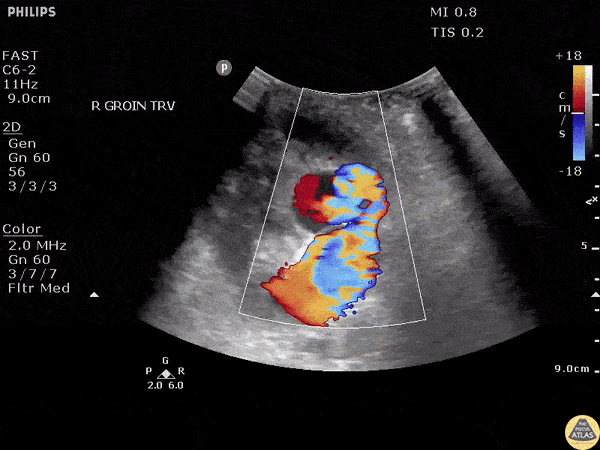

POCUS of a suspected abscess revealed a pseudoaneurysm of the femoral artery. Note the “Pepsi sign” on color doppler made by the turbulence of the blood entering the pseudoaneurym. Image courtesy of Robert Jones DO, FACEP @RJonesSonoEM Director, Emergency Ultrasound; MetroHealth Medical Center; Professor, Case Western Reserve Medical School, Cleveland, OH View his original post here